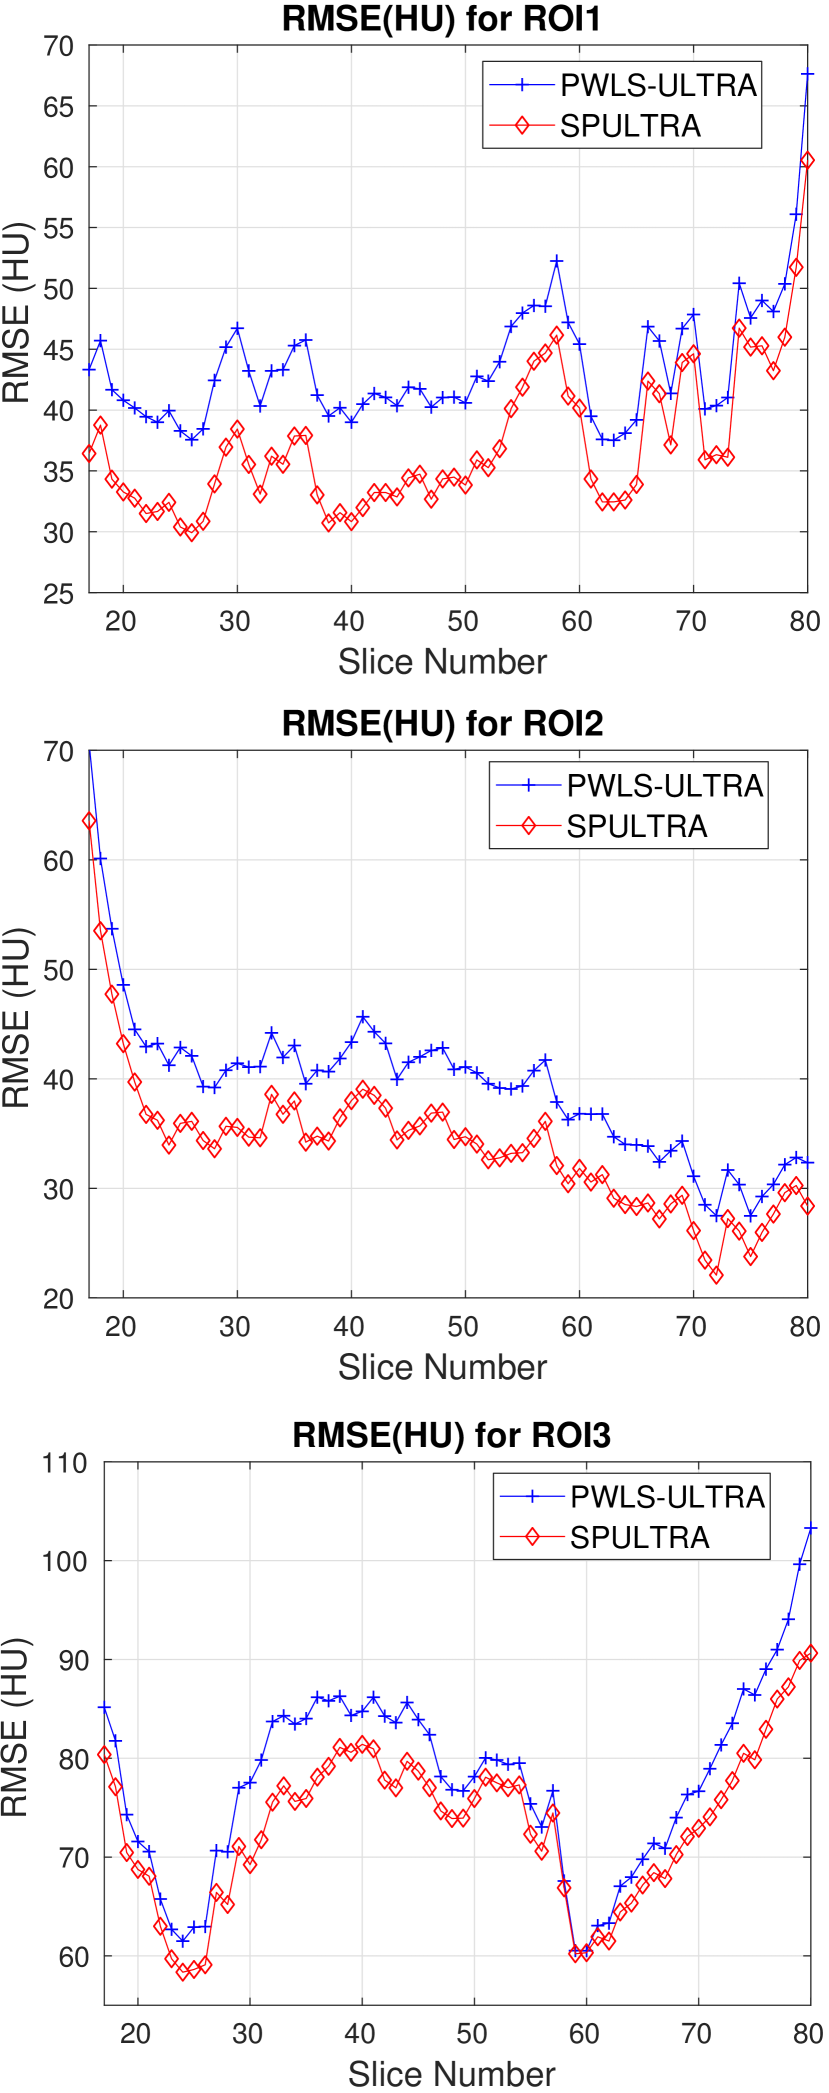

Fig. 4 shows the reconstructed images and the corresponding error images for PWLS-EP, PWLS-ULTRA, and SPULTRA, at and . Compared to the PWLS-EP result, both PWLS-ULTRA and SPULTRA achieved significant improvements in image quality in terms of sharper reconstructions of anatomical structures such as bones and soft tissues, and suppressing the noise. However, the PWLS-ULTRA method introduces bias in the reconstructions, which leads to larger reconstruction errors compared to the proposed SPULTRA method. In Fig. 4, we marked three 3D ROIs in the axial plane, i.e., ROI 1, ROI 2, and ROI 3. Fig. 5 shows the zoom-in images of a 3D plot of ROI 1, and those of ROI 2 and ROI 3 are shown in the supplement. We also plot the evolution of RMSE through the axial slices of the three 3D ROIs in Fig. 6. The figures demonstrate that SPULTRA clearly outperforms the competing PWLS-EP and PWLS-ULTRA schemes.

The RMSE improvement of SPULTRA over PWLS-ULTRA can be more clearly observed from Fig. 3 that shows the RMSE evolution with the number of outer iterations under different dose levels. At low-doses, SPULTRA decreases the RMSE more quickly (from the same initial value) and to much lower levels than PWLS-ULTRA. Fig. 3 shows that to achieve the same RMSE as PWLS-ULTRA at 600 outer iterations, SPULTRA takes 487, 365, 251 and 133 outer iterations under , respectively.